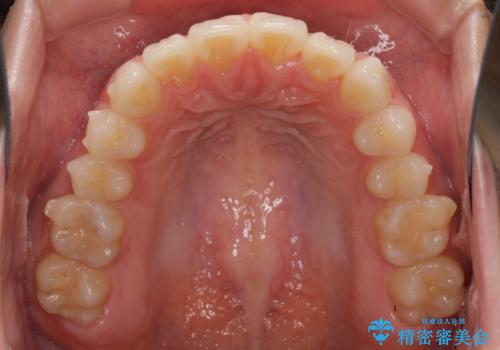

デコボコで飛び出した前歯をきれいに インビザラインによる矯正治療

- デコボコと飛び出した前歯を治したいとのことで来院された患者様です。

ゴムかけを活用して上顎歯列全体を後方移動し、IPR(歯と歯の間を削る)によってデコボコが解消するように設計し、インビザラインにより治療を行うこととしました。

毎日しっかりと装着してくださったので、概ねシミュレーション通りに歯を移動させることができました。

治療前には接触することのなかった上下の前歯が接触するようになり、食事の際前歯でものをかみ切れるようになりました。

気にしていた口元の印象が改善され、患者様には大変満足していただきました。